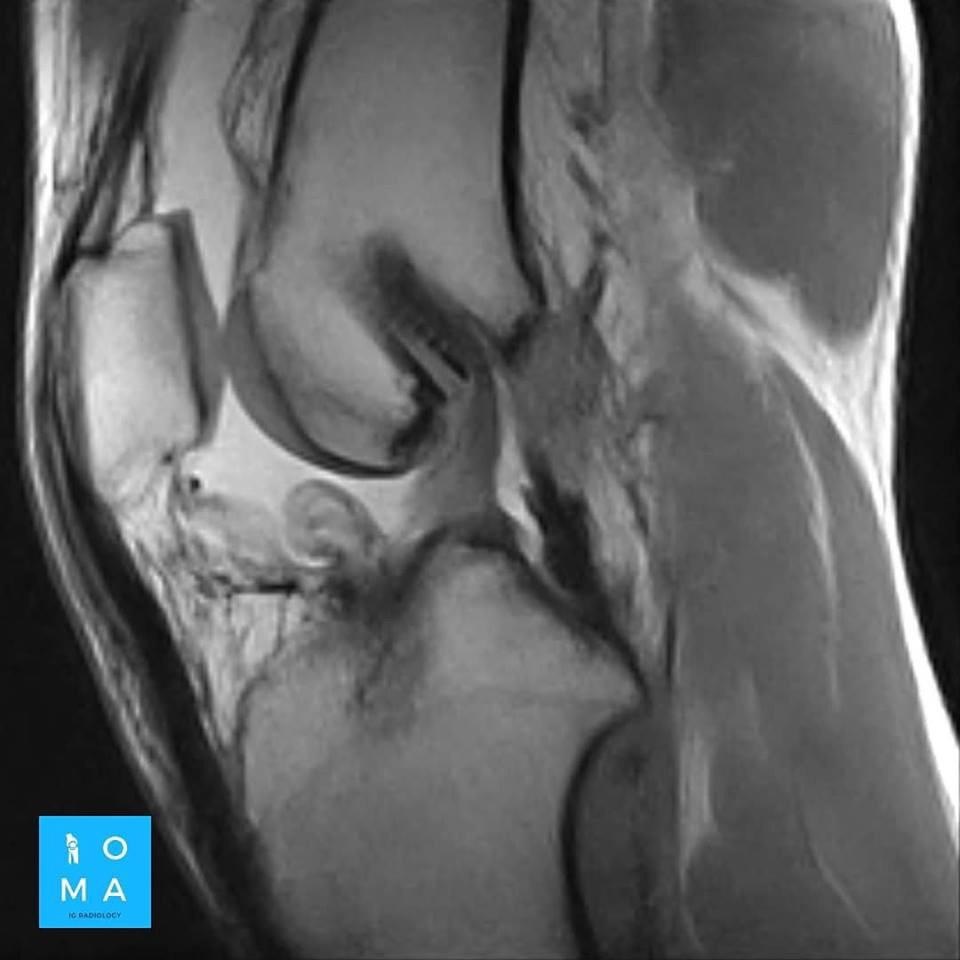

La evaluación hepatica entre Adenoma y HNF por resonancia magnética y su diferenciación con hepatocarcinoma puede ser difícil en ciertos casos aún, con el uso de contraste hepato especifico.

Se presenta caso de paciente de la 3a década, que en su embarazo se diagnostica con sospecha de adenoma y posterior al embarazo se realiza estudio de control contrastado para su mejor diferenciación.

En la evaluación con medio de contraste, se evalúa la relación arterial y de las venas, esto puede servir para buscar la arteria central relacionada con la hiperplasia nodular focal o bien, para evaluar la relación con las estructuras vasculares que son muy importantes para el planeamiento quirúrgico .

en este caso, aún cuando los hallazgos son atípicos tanto para hiperplasia nodular focal como para adenoma, nos inclinamos hacia el diagnóstico de adenoma debido a los antecedentes de la paciente, el tamaño de la lesión, el área de sangrado, el contenido de grasa.